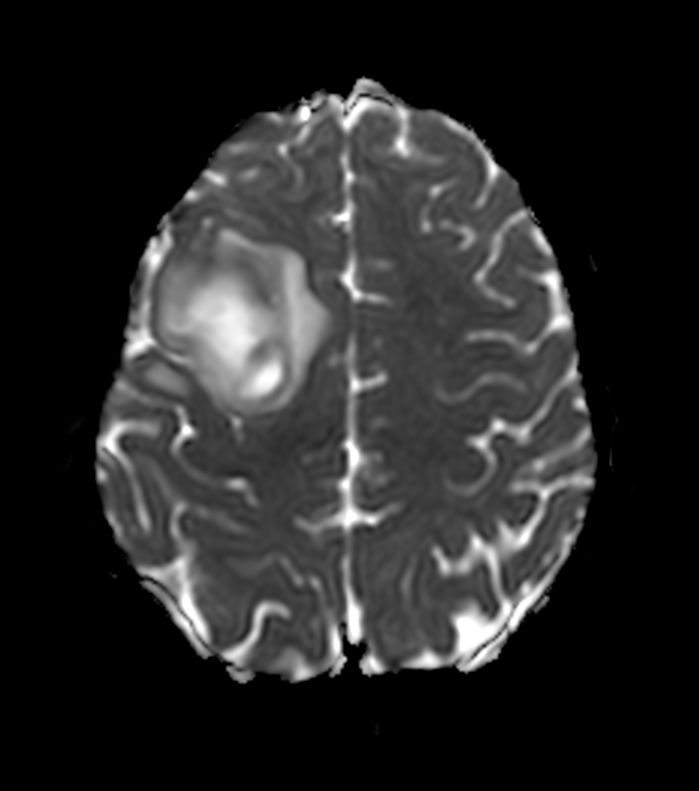

Diffusion (ADC)

Patient with a brain lesion. ExamCard includes MultiVane XD for motion-free imaging in short scan time, Compressed SENSE to shorten exam time, SWIp to enhance contrast for deoxygenated (venous) blood or calcium deposits, a high resolution 3D FLAIR sequence enabling reformats in any plane without loss of resolution, diffusion to achieve high contrast between background and lesions, pCASL to visualize brain perfusion and functional physiology in a non-contrast manner, dynamic multi-slice T2* perfusion for quantitative analysis, and spectroscopy for a non-invasive measurement of biochemical changes in the brain.